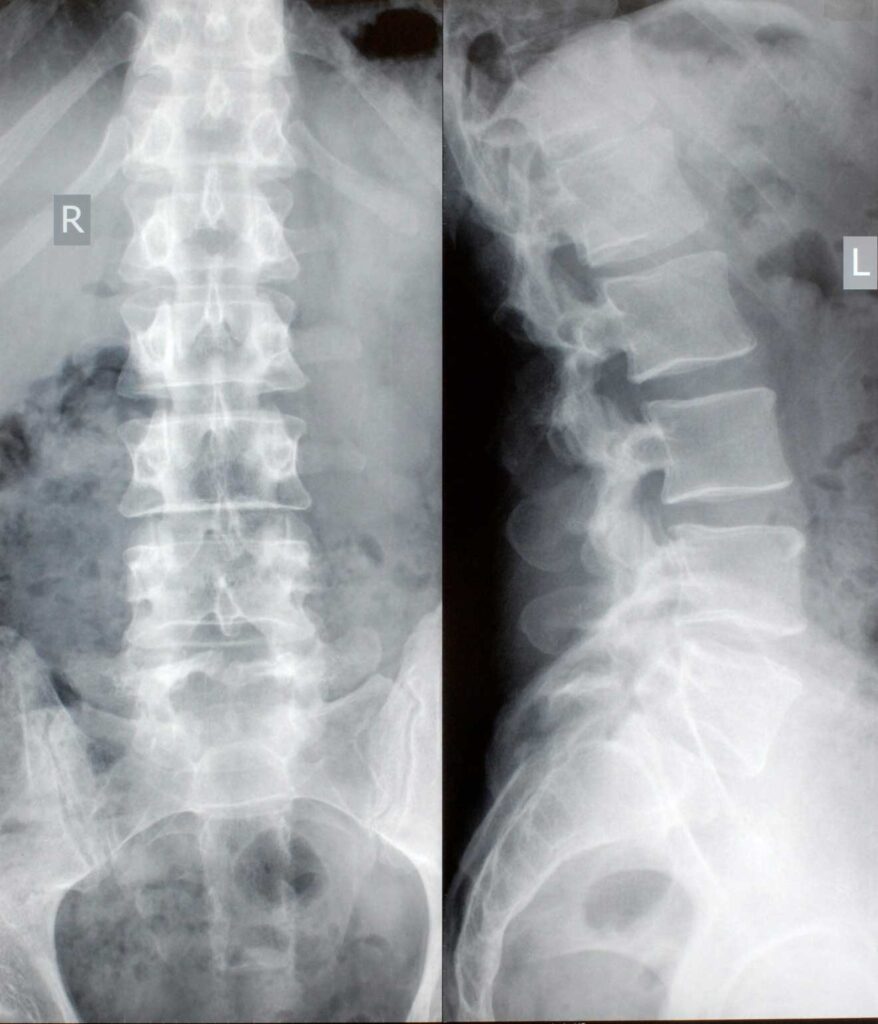

Osteoporosis, on the other hand, is a silent but serious condition characterised by reduced bone mass and deterioration of bone quality, making bones fragile and prone to fractures even after minor falls or trauma. It most commonly affects the spine, hip, and wrist and often remains undetected until a fracture occurs.

Although arthritis and osteoporosis are distinct conditions, they frequently coexist, especially in older adults. Chronic joint pain and stiffness from arthritis can limit physical activity, which in turn accelerates bone loss and worsens osteoporosis. Similarly, weak bones increase the risk of fractures around arthritic joints, complicating treatment and recovery.

Effective management therefore requires a coordinated and comprehensive approach, addressing both joint health and bone strength. Early recognition, regular assessment, and tailored treatment are essential to reduce pain, maintain mobility, prevent fractures, and preserve independence, ensuring better long-term musculoskeletal health.